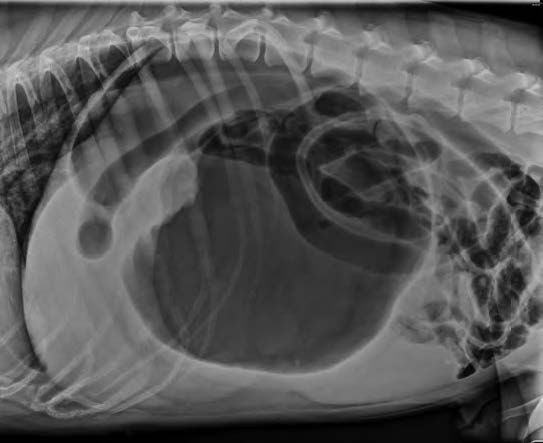

–右侧位通常显示胃部因气体/液体膨胀,并出现分隔(也称为反向C形、双气泡征或“大力水手”征)(图1)。

图1. 狗GDV的右侧腹部X光片。